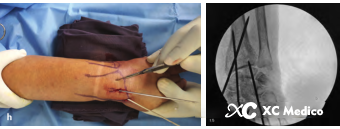

11. При использовании дорсальных и пальмовых проводов Киршнера для лечения заманированных переломов дистального радиуса, если ладонный фрагмент лунной ямки не уменьшается во время операции, вы можете использовать подход ладони, используйте сосудистый зажим, чтобы отделить кость, а затем вставить проволоку Киршнера от фрагмента фрагмента пальмара в доррсовый каркас. (Рисунки ах ниже)

12. Для явно вытесненных переломов дистального радиуса, которые не могут быть уменьшены путем замкнутого восстановления, можно использовать проволоку на 3 мм Киршнера для поднятия дистального фрагмента перелома с задней части для достижения восстановления (рисунки ах ниже).